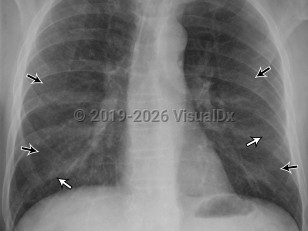

Chest pain, Pleural effusion, 50-59 year old Female

Pleural effusionPleural effusion